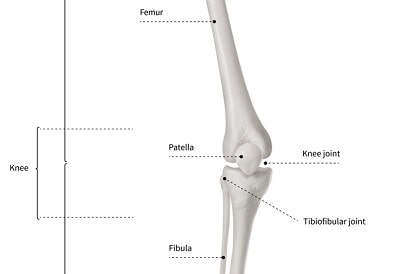

How to tell right and left femur

point head towards you and, the balls on the distal end point posteriorly

ball

Femur Head

location of break

Femur Neck

Greater Trochanter of the Femur

Lesser Trochanter of the Femur

Intertrochanteric crest

only on the back of the femur

Gluteal tuberosity

Adductor tubercle

medial condyle

Lateral epicondyle

Not arrow Condyle

Lateral Condyle

Medial Epicondyle

behind patella on femur

Patellar Surface

Poplitheal Surface

Patella is in what tendon

Quadriceps femoris mm